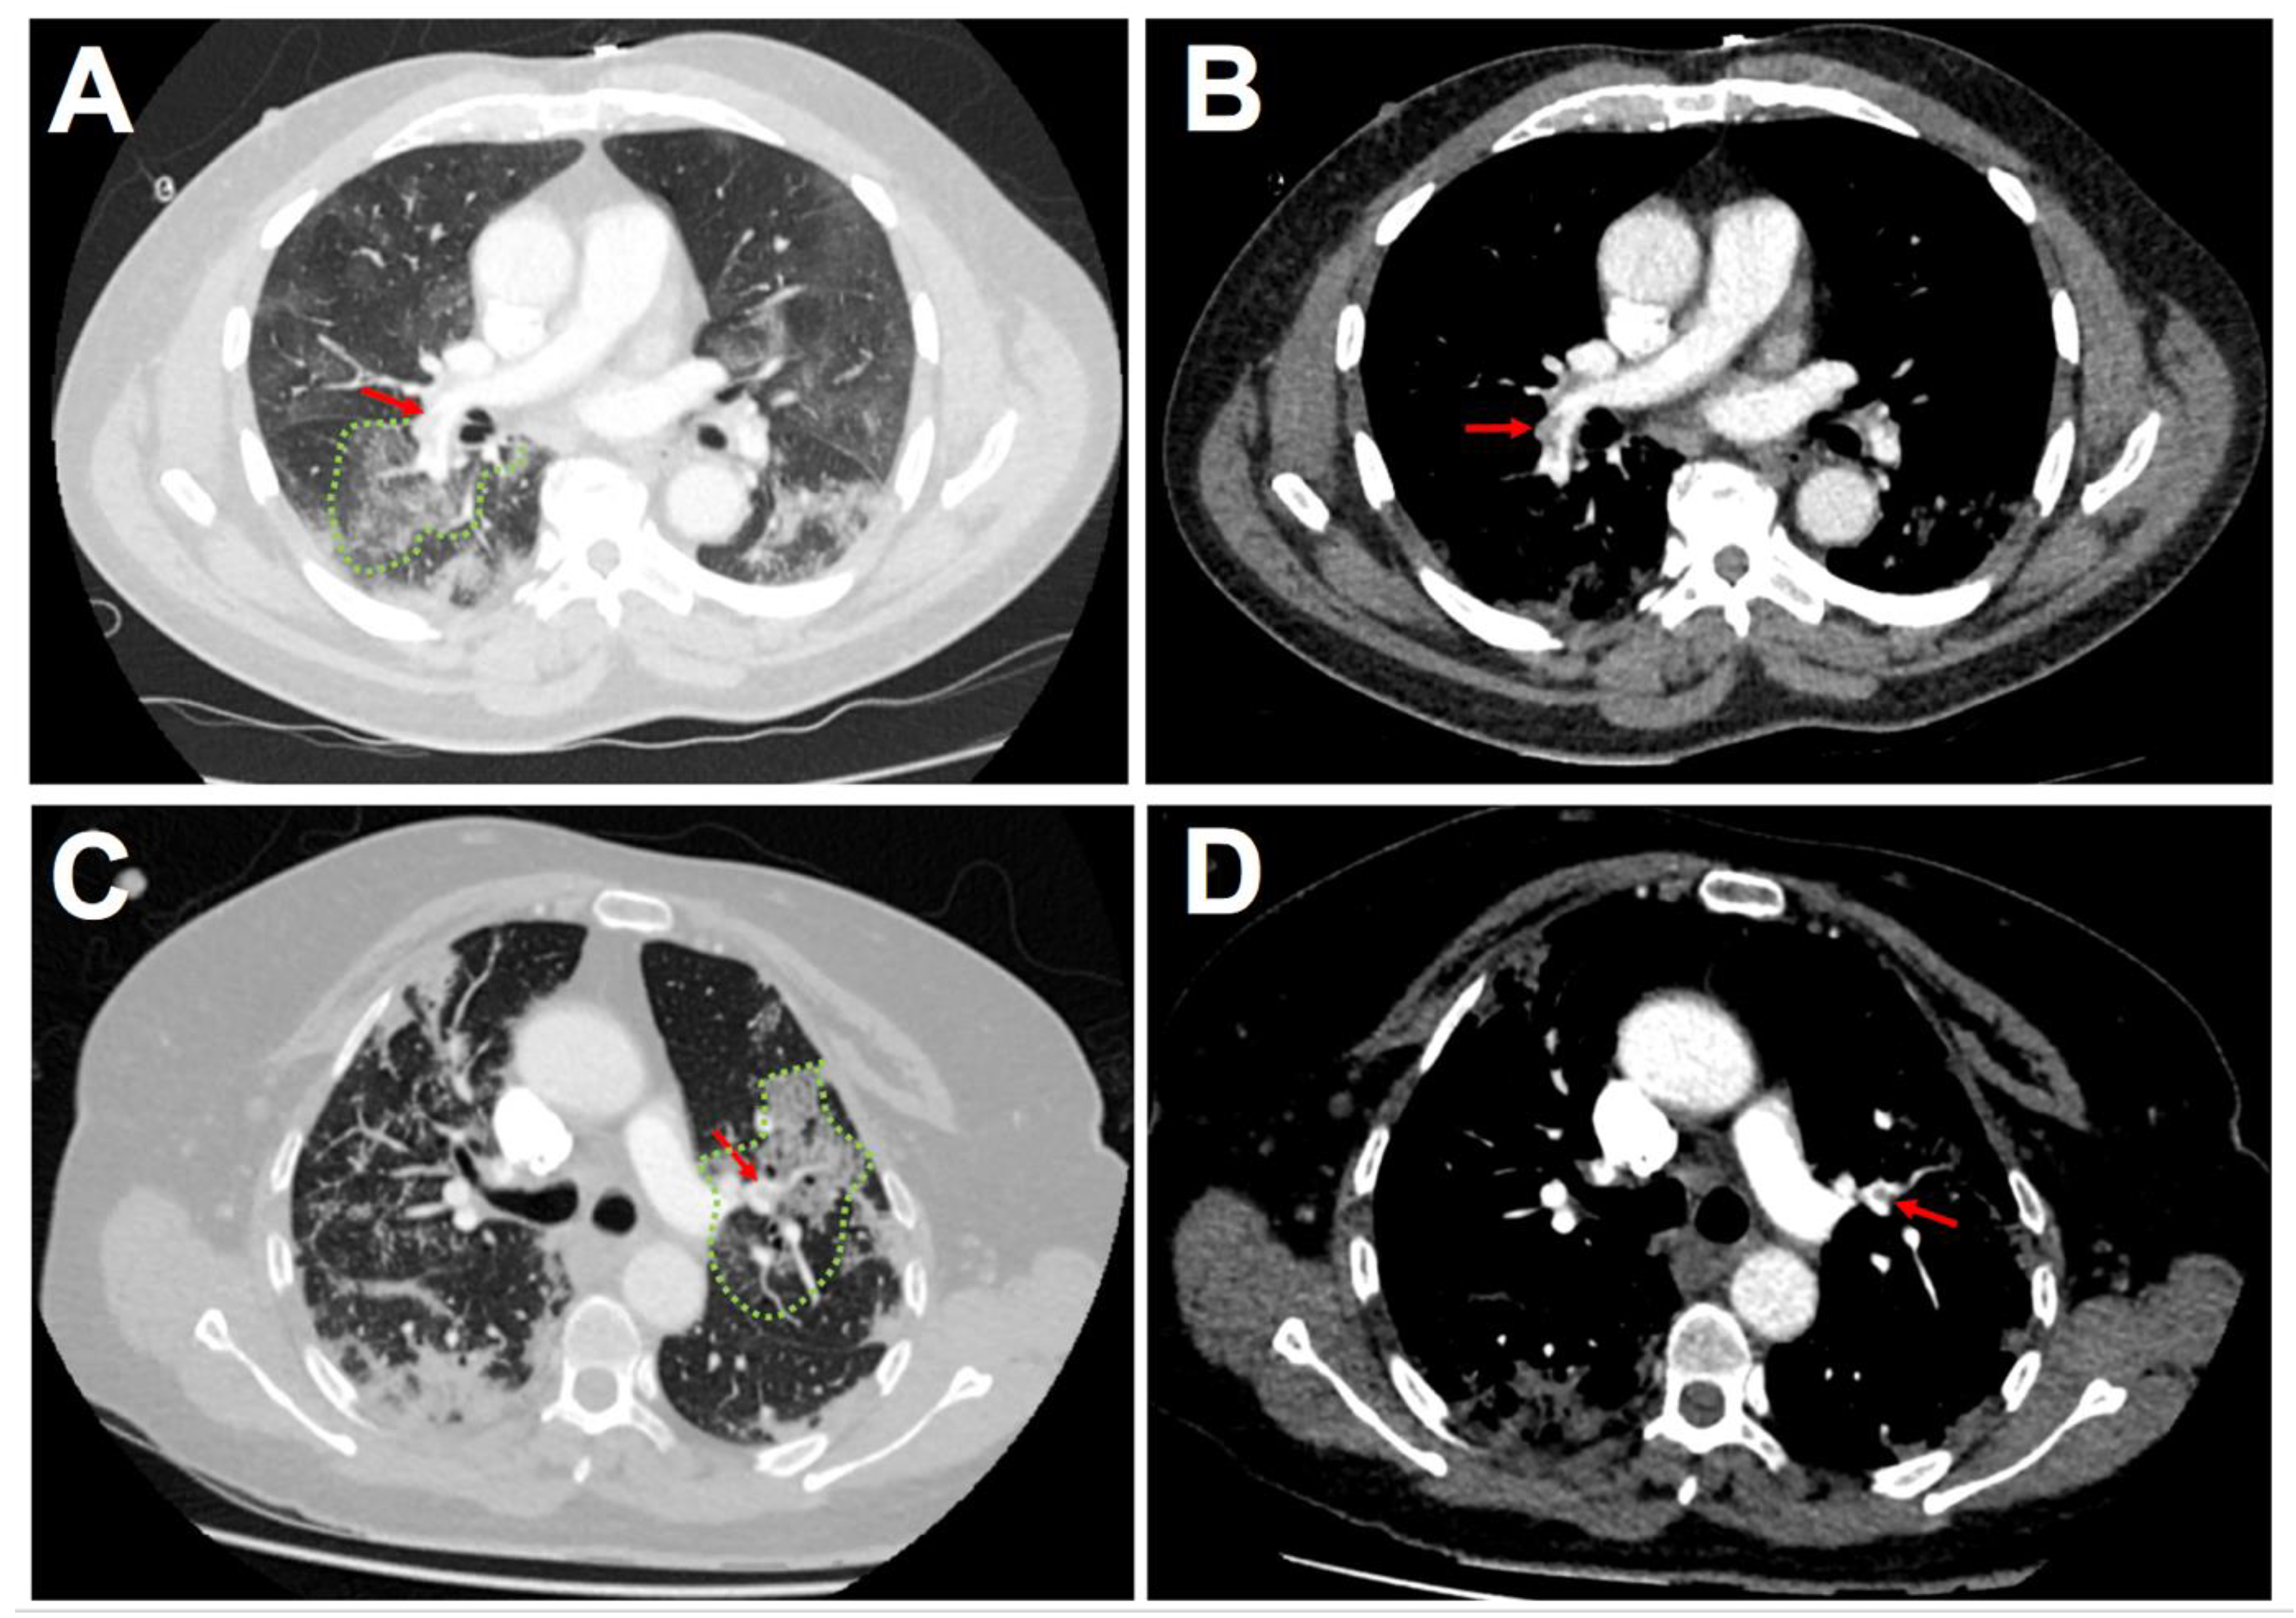

3.2. Imaging of Acute Pulmonary Embolism

| APE localization | |||

| Sub-segmental–n (%) | 9 (11.1) | 6 (10.2) | 0.859 |

| Segmental–n (%) | 20 (24.7) | 21 (35.6) | 0.162 |

| Lobar–n (%) | 26 (32.1) | 15 (25.4) | 0.391 |

| Troncular–n (%) | 26 (32.1) | 17 (28.8) | 0.677 |

| Co-localization between segmental or subsegmental thrombus and COVID-19 related lung injuries–n (%) | - | 27 (100) | - |

| Thrombus load assessment | |||

| Qanadli score–IU | 9.0 ± 7.4 | 8.1 ± 6.9 | 0.452 |